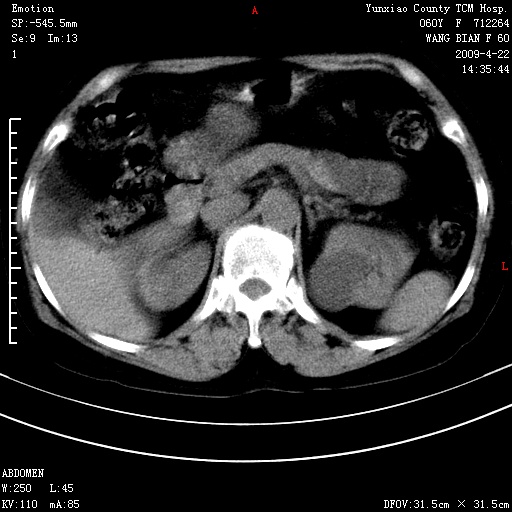

蛛网膜颗粒压迹 左肾低密度影囊肿可能。

不出外肾癌,强化下看

2、左肾囊肿。

脑正常,肾有事,须强化,再定性.

1、头颅未见明显异常。2、左肾囊肿可能。建议增强

1、枕骨蛛网膜粒压迹。2、左肾囊肿可能。建议增强

头颅未见明显异常。左肾囊肿。

1)枕骨蛛网膜粒压迹。2)左肾囊肿可能。

不出外肾癌,强化下看,枕骨蛛网膜粒压迹。

2、左肾囊肿可能性大。